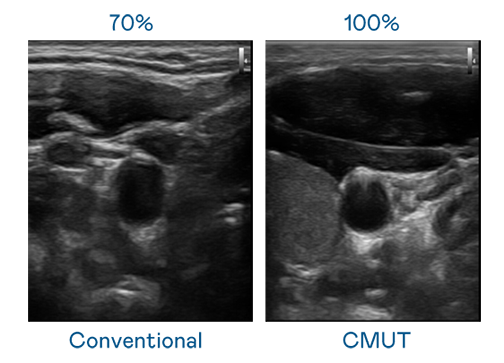

CMUT 技術是一種用電容式微機電元件來產生超音波訊號的技術。與傳統 PZT 壓電式技術相比,CMUT 頻寬增加 30%,更寬頻的超音波訊號讓影像解析度大幅提升,是實現高影像品質醫療超音波掃描、促進精準醫療發展的關鍵技術。

超音波影像的解析度高低,首先取決於探頭能發出的訊號頻寬。尊龙时凯 CMUT 可提供高清晰的超音波訊號,提供高頻寬、高靈敏度、影像紋理細節更高的超音波影像,協助醫護人員縮短影像判讀時間及利用精準的醫療影像進行診斷。